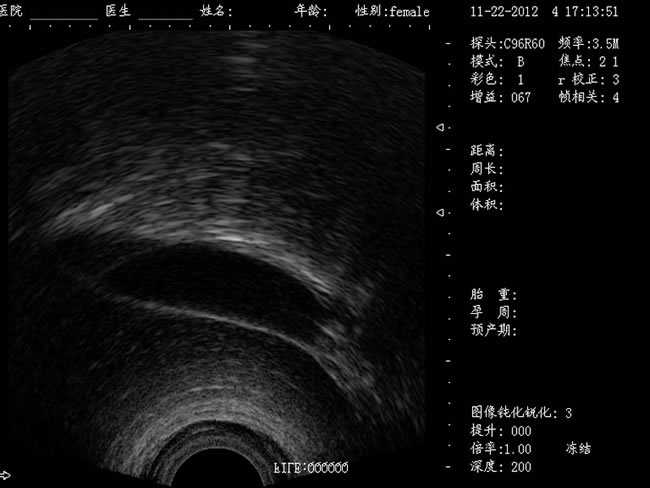

DW-460全數字超聲婦產科手術監視儀

DW-460

婦產科手術監視儀-可視人流機掃描角度:

a) 6.5MHz腔內探頭:152º可視可調;

b) 3.5MHz凸陣探頭:60º可視可調;